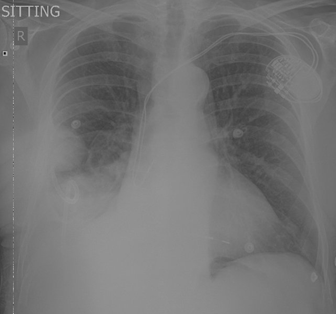

Mr X, an 87-year-old South African male

with a background history of malignant melanoma (excised in 1982), in

remission; presented with shortness of breath and a cough. He was a non-smoker

and of sober habits and had a history of a pacemaker inserted for a

tachyarrhythmia. He had no other comorbidities. An initial baseline chest X-Ray

(CXR) performed on 26 May 2024 revealed a right pleural effusion (Figure 1).

This caused the shortness of breath in the patient and was considered treatable

as the fluid could be drained, which would lead to symptomatic relief.

Figure 1. CXR performed on 26 May 2024.